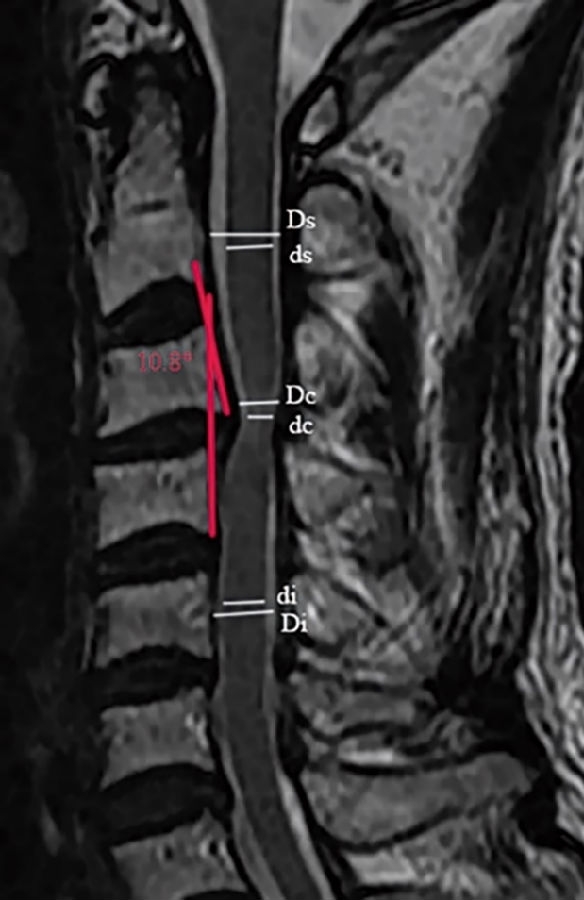

3.1颈椎MRI矢状位脊髓压迫比值

依据Fehlings等报道的方法测量颈椎MRI矢状位脊髓压迫比值(compression ratio of the spinal cord,CRS)。分别测得颈椎MRI矢状位,压迫程度最重节段脊髓直径(dc),上方椎体水平非压迫节段脊髓直径(ds)以及下方椎体水平非压迫节段脊髓直径(di)(图1)。其中选择MRI正中矢状位或旁矢状位测量,依据颈椎间盘压迫位置,分为中央型与旁中央型。CRS具体测量公式如下:

3.2 颈椎间盘突出程度

颈椎间盘突出程度依据颈椎MRI矢状位椎管压迫比值(compression ratio of the cervical spinal canal,CRCS)。椎管压迫比值CRCS与脊髓压迫比值CRS测量方法类似,只是前者测量的是椎管整体压迫程度,后者关注的是脊髓本身压迫程度。分别测得颈椎MRI矢状位压迫程度最重节段椎管直径(Dc),上方椎体水平非压迫节段椎管直径(Ds)以及下方椎体水平非压迫节段椎管直径(Di)(图1)。CRCS具体测量公式如下:

图1.颈椎MRI矢状位脊髓压迫比值和颈椎间盘突出程度的测量方法。颈椎MRI矢状位,压迫程度最重节段脊髓直径(dc),上位椎体水平非压迫节段脊髓直径(ds)以及下位椎体水平非压迫节段脊髓直径(di);压迫程度最重节段椎管直径(Dc),上位椎体水平非压迫节段椎管直径(Ds)以及下位椎体水平非压迫节段椎管直径(Di)

颈椎节段后凸角度测量使用Harrison椎体后切线法,此测量方法相较Cobb角法对颈椎后凸的评估更可靠。本研究中,我们尝试探索退变性颈椎后凸对神经功能的影响,Harrison椎体后切线法更直接评估椎体后缘成角而非椎体上下终板交角对脊髓的影响,可能会提高测量结果与脊髓神经功能损害程度的相关性(图1)。分别测量了在颈椎MRI矢状位像上、颈椎侧位X线、过屈位X线及过伸位X线上的颈椎节段角度。本研究中颈椎前凸角度定为负值,颈椎后凸角度定为正值,以°为标准界定颈椎后凸。